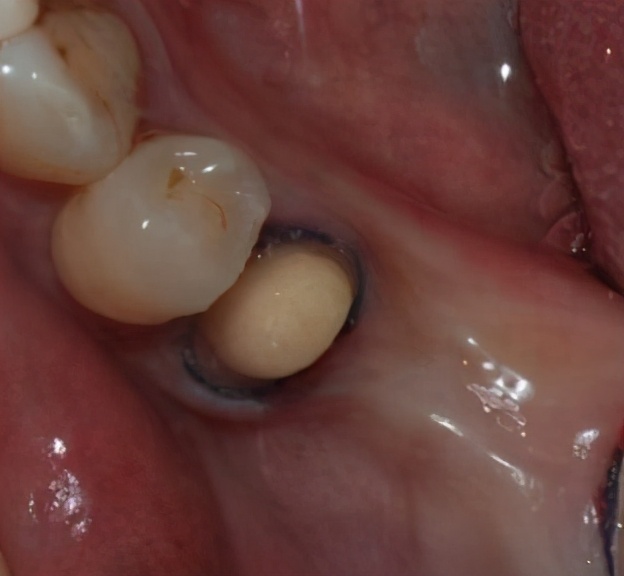

4、牙冠损坏

在某些情况下,会在口腔中多种力量的作用下使得牙冠遭受到损坏,一旦遭受损坏则会逐渐形成裂缝,最终使得牙冠与牙齿之间的密封部位发生了松动,导致牙冠脱落。